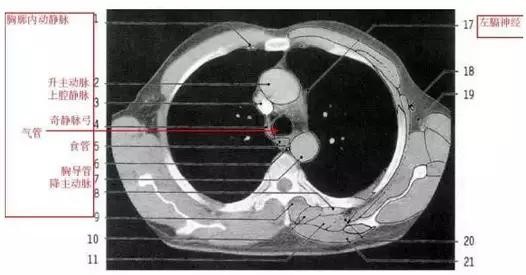

胸部的CT是通过X线计算机体层摄影(CT)对胸部进行检查的一种方法。正常胸部CT层面较多,每一层面结构所表现的图像不同。下面是胸部CT图文示意图,可帮助临床医生详细了解CT结构。我们一起来看一下吧。